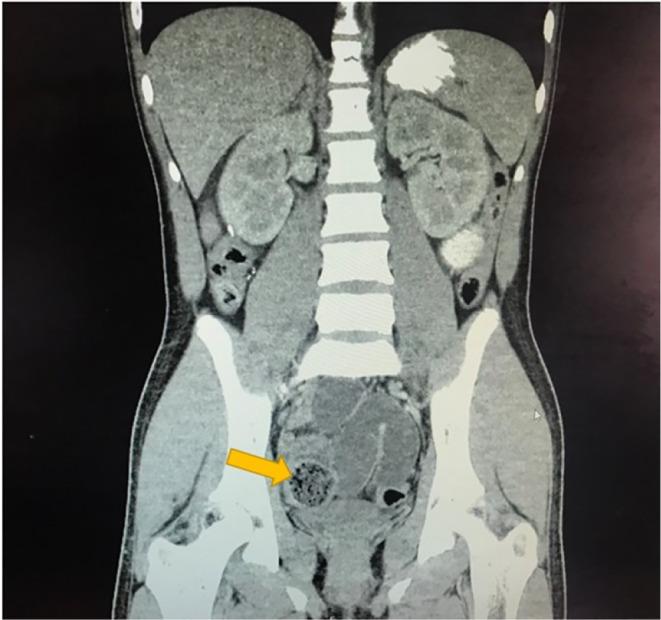

Bezoars are solid masses of undigested material that can cause obstruction of the gastrointestinal tract. There are different types of bezoars; phytobezoar, trichobezoar, pharmacobezoar, lactobezoar, and bezoars containing tissue paper or polystyrene foam. This case report is of a 13-year-old Hispanic male who suffered a postsurgical complication after removal of bezoar. He had a past surgical history of appendectomy and presented to the hospital with a 1-day history of right lower quadrant abdominal pain associated with fever and diarrhea. X-radiation images and computed tomography scans aided in the diagnosis of pelvic abscess as a complication of postsurgical enterotomy and closure of the enterotomy to remove bezoar from the small bowel. The initial bezoar removal and the postsurgical complication of pelvic abscess resulted in the patient staying for 19 days in the hospital. At discharge, the patient and his guardian were advised to follow up with the patient's primary care physician and surgical team. The patient made an uneventful recovery. He did not experience any long-term complications and fully recovered. This report demonstrates that although bezoars are rare, they can cause significant obstruction of the gastrointestinal tract leading to the need for management, such as surgery, which carries its own risks. It is important to note that the postsurgical complication of pelvic abscess can occur due to surgery itself and not because of bezoar specifically. Abdominal surgery in general poses the risk of pelvic abscess. The consideration is to expectantly decrease the occurrence of bezoars so that consequently there will not be a need for surgery in removal of bezoars due to obstruction. The effects of bezoars can be prevented through educating the community and addressing underlying psychiatric disorders.

胃石是未消化物质形成的固体团块,可导致胃肠道梗阻。胃石有不同类型,包括植物性胃石、毛发胃石、药物性胃石、乳凝块胃石以及含有卫生纸或聚苯乙烯泡沫的胃石。本病例报告的是一名13岁西班牙裔男性,在胃石切除术后出现手术并发症。他既往有阑尾切除术史,因右下腹痛伴发热和腹泻1天入院。X线影像和计算机断层扫描有助于诊断盆腔脓肿,这是术后小肠切开取石及肠切开闭合术后的并发症。最初的胃石取出及盆腔脓肿这一术后并发症导致患者住院19天。出院时,建议患者及其监护人随访患者的初级保健医生和手术团队。患者恢复顺利。他未出现任何长期并发症,已完全康复。本报告表明,尽管胃石罕见,但可导致胃肠道严重梗阻,从而需要进行手术等治疗,而手术本身也有风险。需要注意的是,盆腔脓肿这一术后并发症可能是手术本身所致,而非专门由胃石引起。一般来说,腹部手术有发生盆腔脓肿的风险。应考虑期望减少胃石的发生,从而避免因梗阻而需要进行胃石切除术。通过对社区进行教育和解决潜在的精神障碍问题,可以预防胃石的影响。